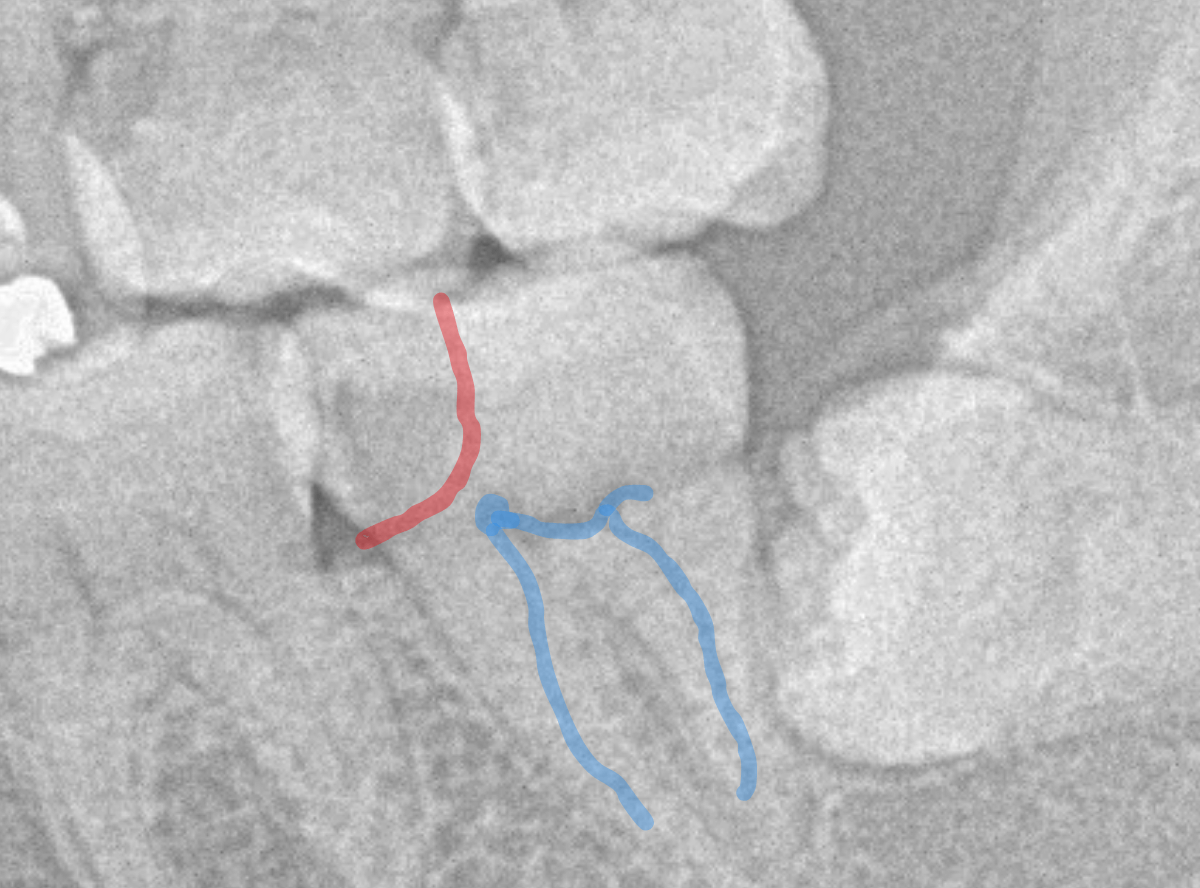

レントゲン写真で確認します。

青い線が歯の神経です。

赤い線が虫歯と思われる部分です。

思った通り、神経に達してしまいそうな大きな虫歯です。

患者さんには、神経を取る治療が必要な可能性が高い事を説明します。